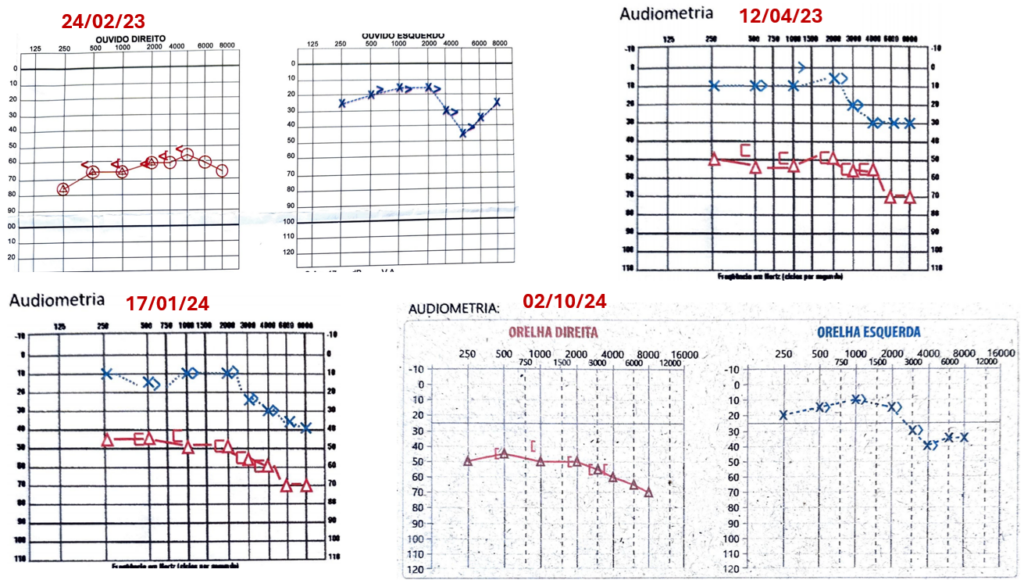

Se compararmos as imagens acima dos exames audiométricos, podemos ver uma flutuação auditiva por exemplo comparando as audiometrias de fevereiro de 2023 com a de janeiro de 2024.